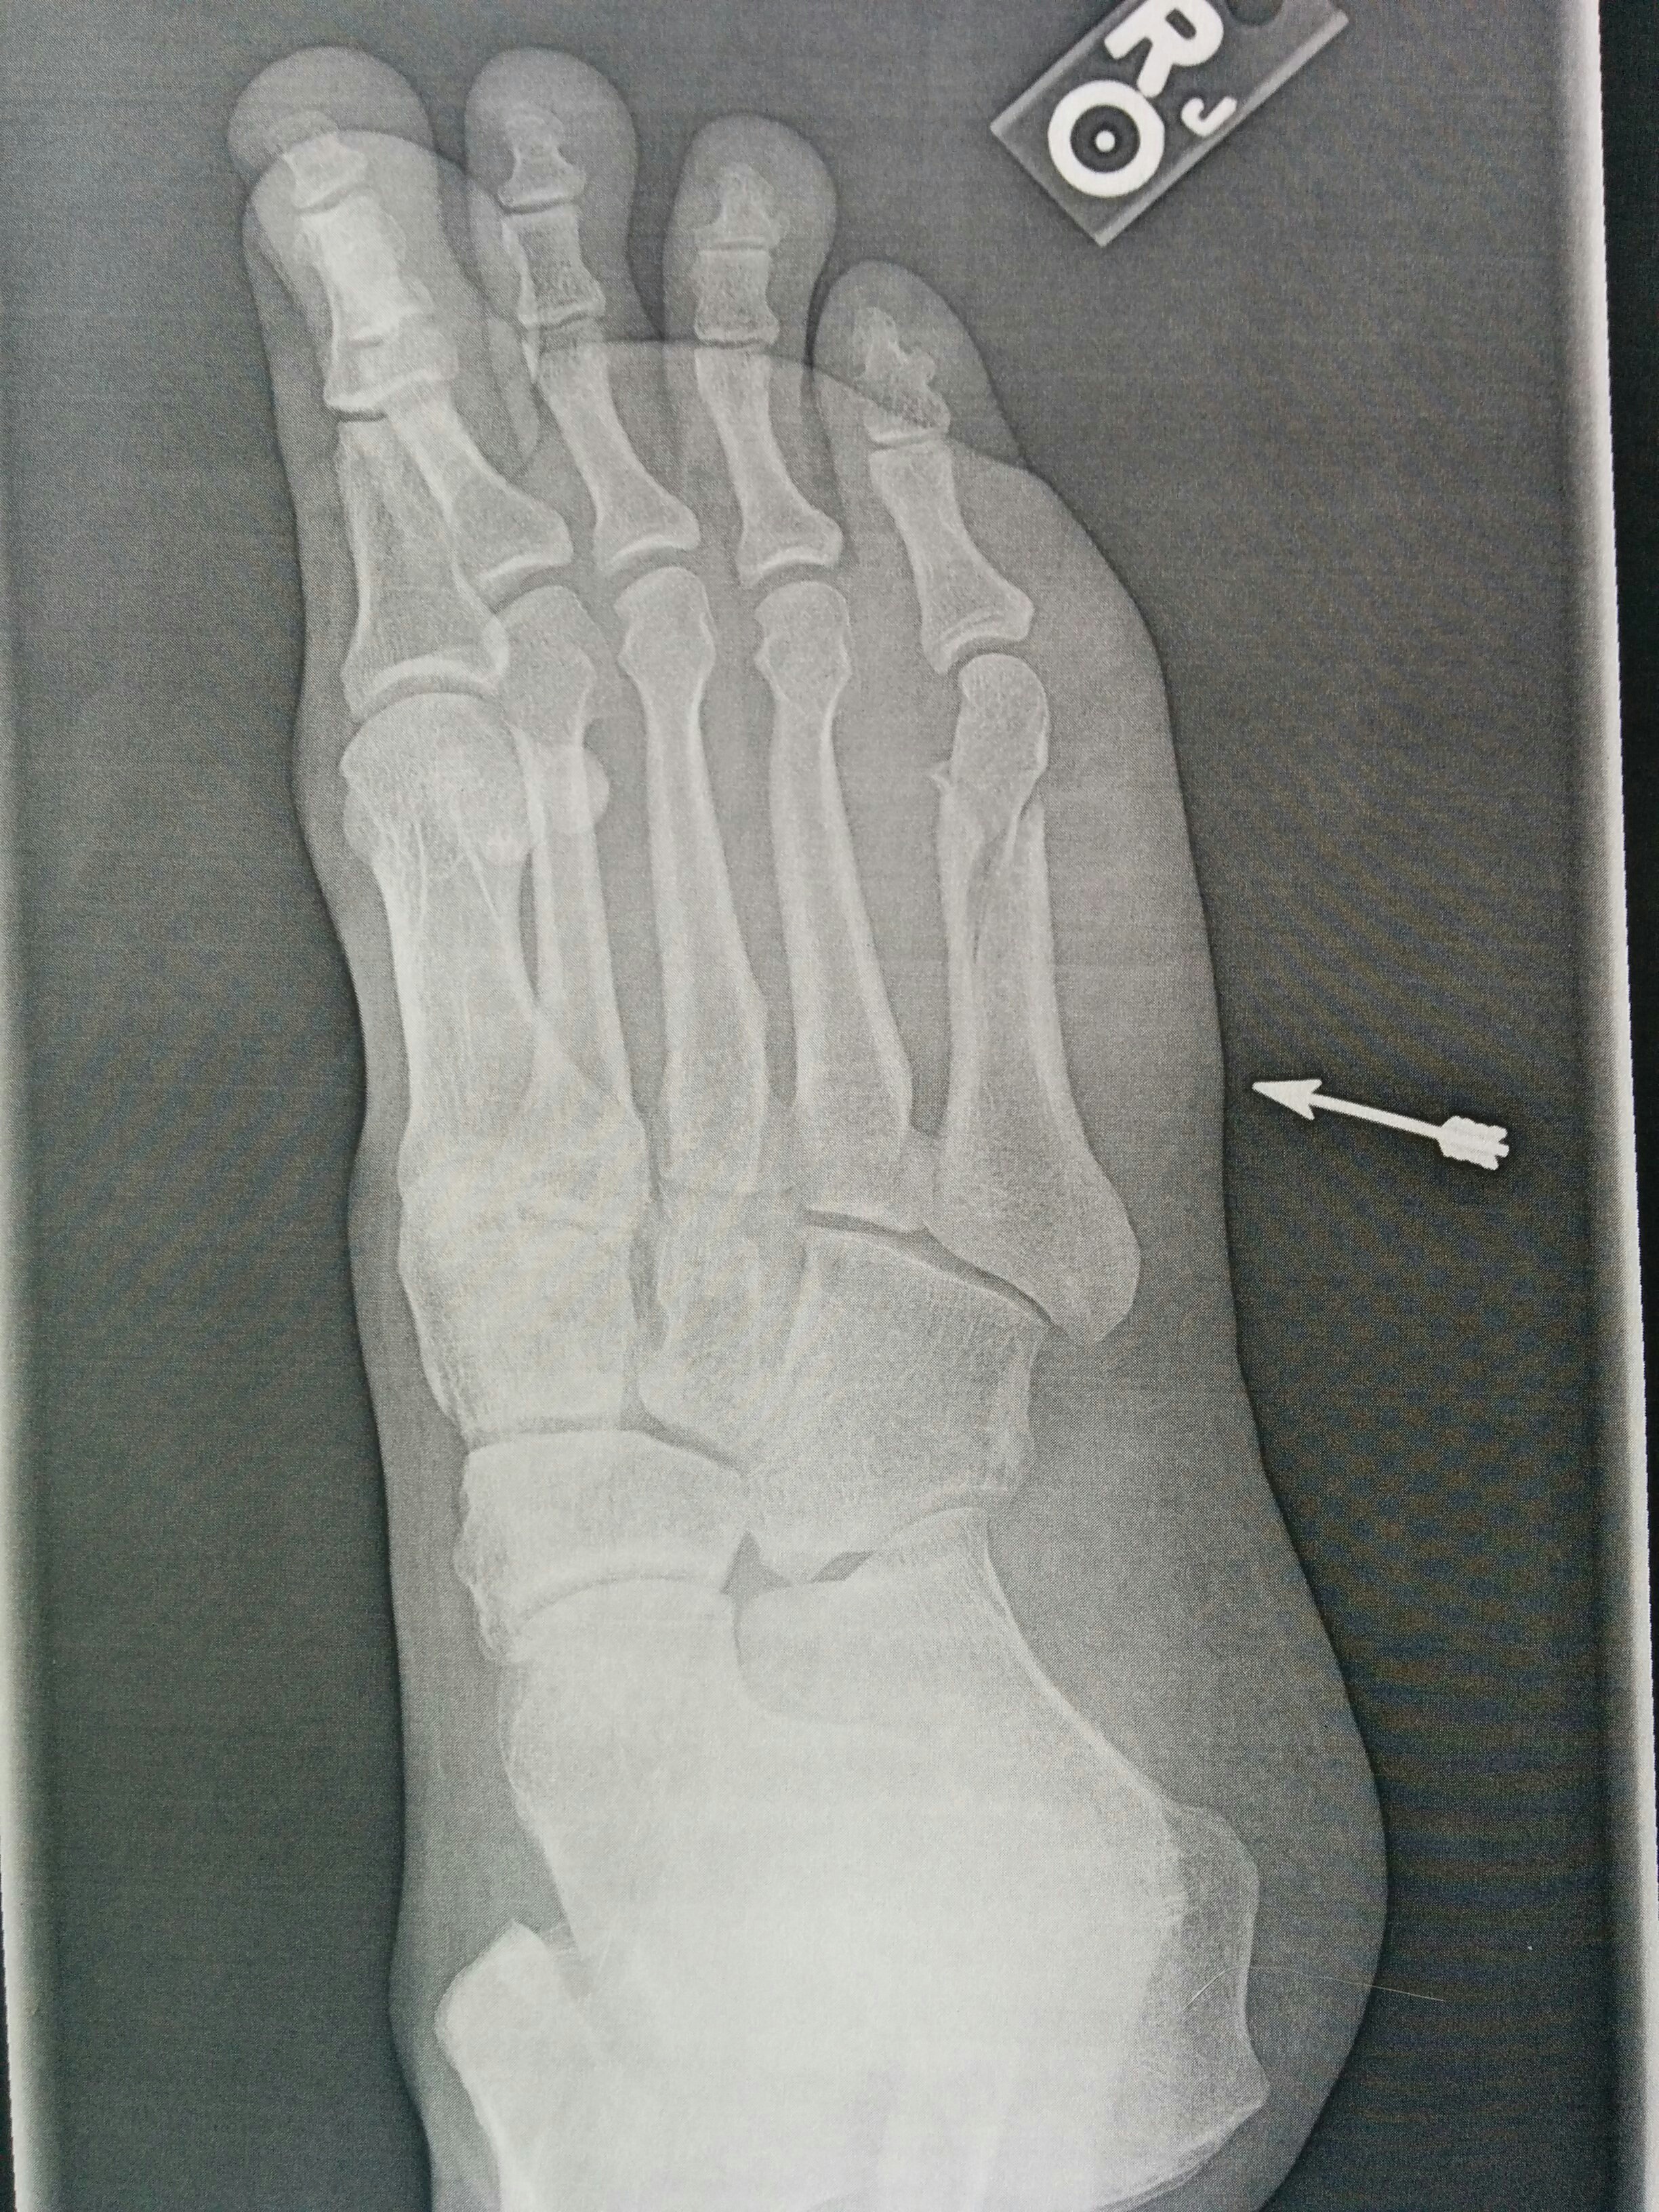

So this happened. I fractured a bone in my right foot. I’m still waiting to find out if it needs surgery or not. Regardless, there will be no working, fishing, driving or even walking for quite a while. That’s probably good news for the blog as I still have some photos outstanding from this summer. Time to exercise my typing muscles!

Metatarsal Malfunction